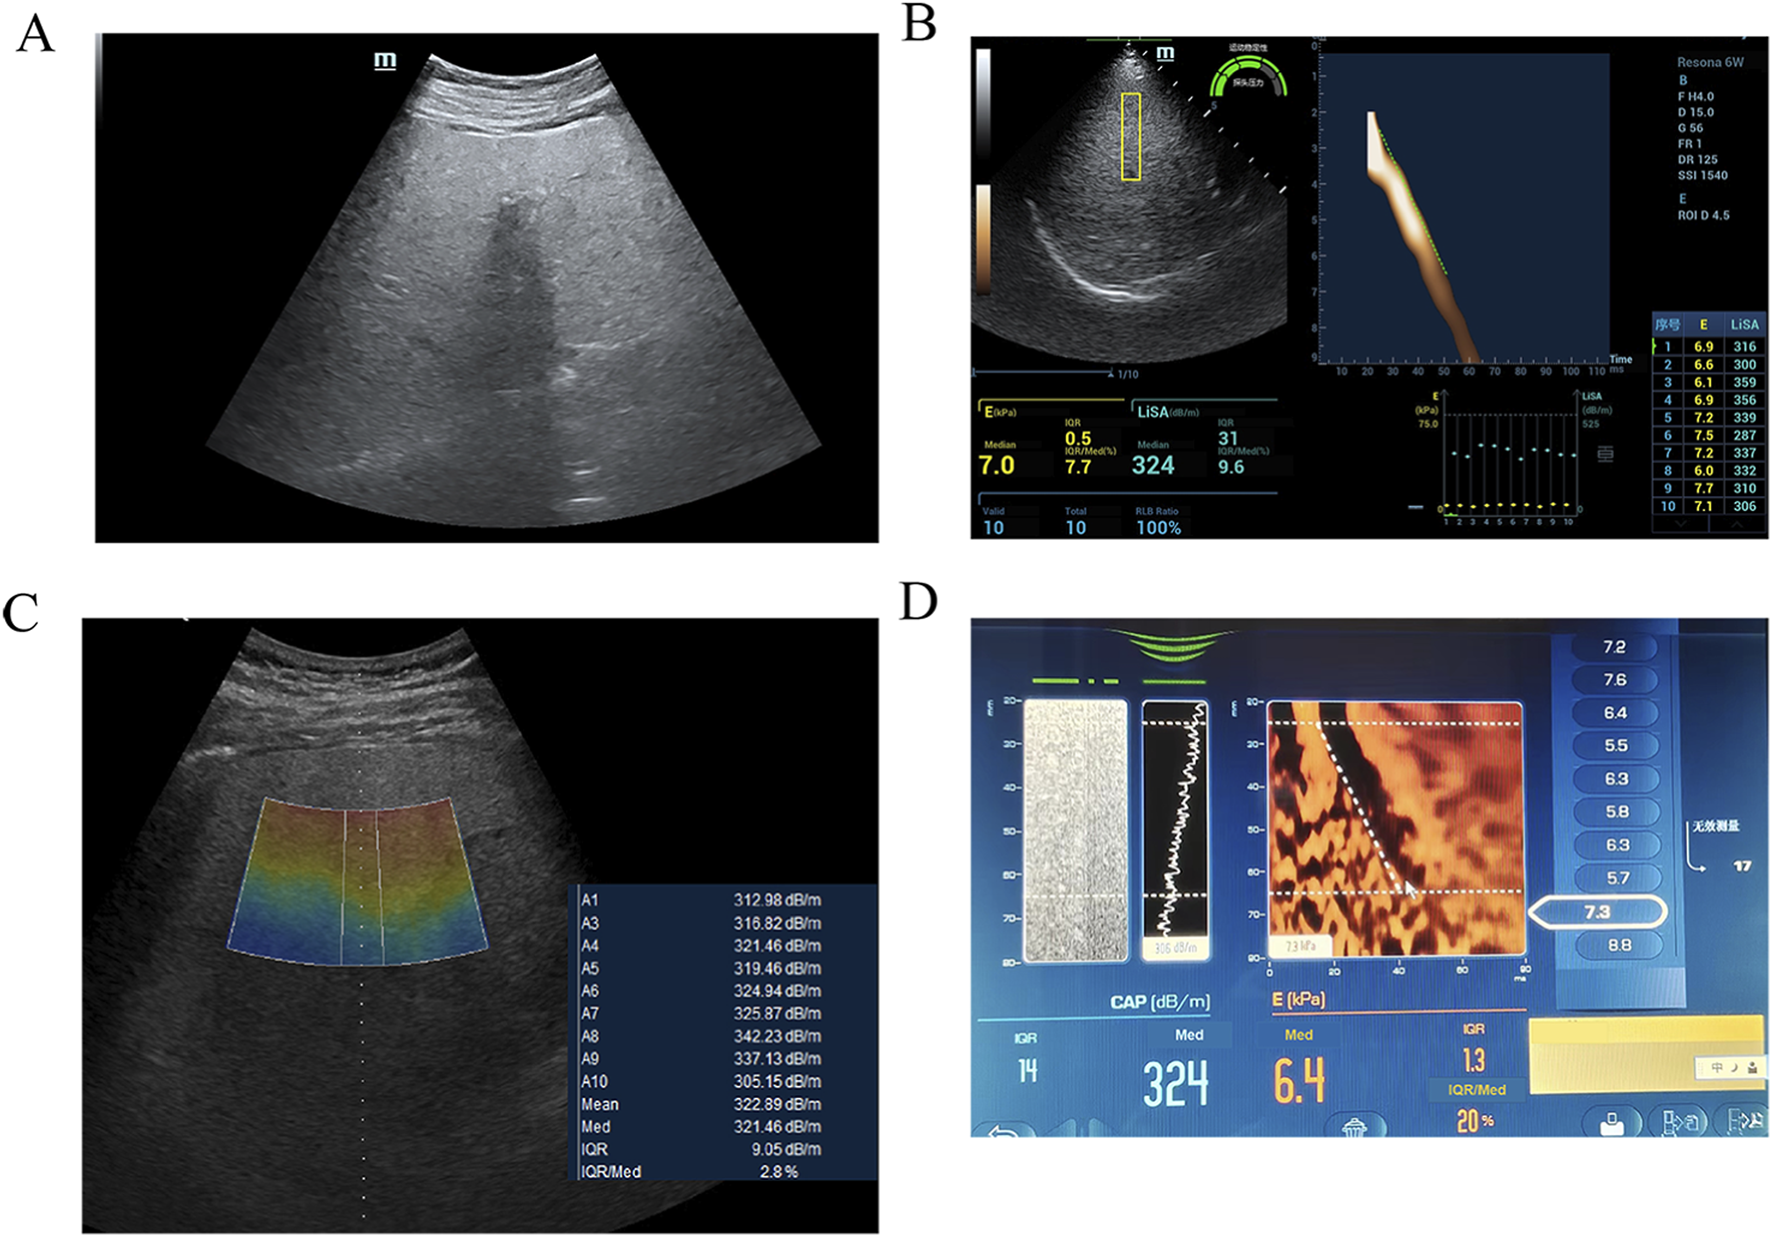

Conventional B-mode ultrasound (Mindray Resona 6w or GE LOGIQ E11) was performed to confirm diffuse hepatic steatosis (increased echogenicity, beam attenuation) and exclude focal lesions or ascites (Figure 1A). A standardized acoustic window in segment V of the right hepatic lobe was selected—homogeneous and free of major vessels or ducts. Skin-to-capsule distance (SCD) was measured from the skin surface to Glisson’s capsule using electronic calipers.

LiSA measurements were performed using a Resona 6w system (Mindray) equipped with an LFP5-1U convex array probe, operating in harmonic imaging mode at a frequency of 4.0 MHz. A rectangular sampling box (4.0 cm × 1.0 cm) was placed at a fixed depth of 4.5 cm (Figure 1B).

UGAP measurements were obtained using a LOGIQ E11 system (GE Healthcare) with a C1-6-D convex array probe, operating in fundamental imaging mode at 3.5 MHz. A trapezoidal sampling region (upper base 1.0 cm, lower base 1.2 cm, height 4.0 cm) was positioned within a depth range of 4–8 cm (Figure 1C).

2.3.3 CAP measurement

CAP was measured using a FibroScan® 502 Touch device (Echosens, France) with an M-type probe. For participants with a SCD ≥2.5 cm, the XL probe is recommended; however, in this study, the M probe was used uniformly to maintain consistent measurement conditions. The measurement site was pre-localized with a handheld ultrasound device (VScan, GE Healthcare) to avoid major ducts. The M probe was placed perpendicular to the skin; measurements started when the probe indicator turned green. At least ten valid measurements (IQR <40 dB/m, IQR/M < 30%) were obtained. The final CAP value was the median of all valid measurements (dB/m) (Figure 1D). Steatosis was graded per manufacturer-recommended thresholds: S0 (<230 dB/m), S1 (230–274 dB/m), S2 (275–299 dB/m), S3 (≥300 dB/m). Although these thresholds are widely accepted clinically, their applicability may vary across different populations. Local validation is recommended when applying these cut-offs in clinical practice.

Imaging findings of severe hepatic steatosis in a 60 year-old female with hypertension. (A) B-mode ultrasound examination indicating severe hepatic steatosis. (B) UGAP measurement by GE LOGIQ E11, the value was 321 dB/m (C) LiSA measurement by Mindray Resona 6w, the value was 324 dB/m (D) CAP measurement by FibroScan, the value was 335 dB/m.